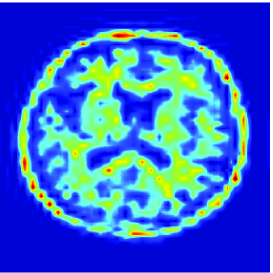

Remark 5.6

At this point, it may be interesting to compare the proposed extension with the approach developed in [24]. The use of the Anscombe transform [2], in [24] is actually tantamount to approximating the anti log-likelihood of the Poisson distribution by

| (50) |

The proposed quadratic extension is illustrated in Fig. 4 where a graphical comparison with the Anscombe approximation is performed.

Here, is a uniform blur with . A () medical image shown in Fig. 5(a) is degraded by and corrupted by a Poisson noise following the model described in the previous section for various intensity levels. The degraded image is displayed in Fig. 5(b) when .

To evaluate the performance of our algorithm we use the Signal to Noise Ratio defined in Section 5.3.2. Tab. 2 shows the values of the obtained for different values of and . As predicted by Proposition 5.4(v), beyond some value of , which is dependent of , the optimal value is found. We also compare our results with those provided by two different approaches. The first one is the regularized Expectation Maximization (EM) approach (also sometimes called SMART) [10, 31] where the Poisson anti-likelihood penalized by a term proportional to the Kullback-Leibler divergence between the desired solution and a reference image is minimized. Its weighting factor has been adjusted manually so as to maximize the and, the reference image is a constant image whose pixel values has been set to the mean value of the degraded image. The other approach is the method based on the Anscombe transform proposed in [24] and discussed in Remark 5.6. For fair comparisons, the method here employs the same orthonormal wavelet representation, the same functions as ours and the same constraint set . It can be observed that the approach we propose gives good results. However, for high intensity levels (), the method based on the Anscombe transform performs equally well in terms of SNR. The restored images are shown in Fig. 5, when and after 3000 iterations. In spite of an important degradation of the original image, it can be seen that our approach is able to recover the main features in the image. It can also be noticed that the image restored by the two methods exhibit different visual characteristics.

![]() |

| (b) | (c) |

| (d) | (e) |